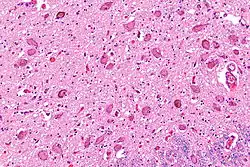

Micrograph showing the locus coeruleus. HE-LFB stain.